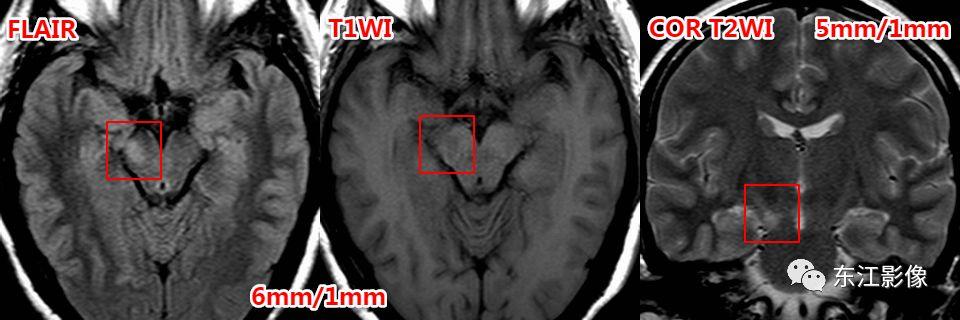

鉴别诊断:

腔隙灶

- 当扩大的血管周围间隙部位、形态、信号典型时,鉴别诊断非常容易。

- 当扩大的血管周围间隙部位、形态、信号不典型时,鉴别有一定的难度。

- 薄层扫描有助于这类小腔隙样灶的鉴别。

- 腔隙灶多为软化灶,FLAIR边缘多呈高信号,边缘不光整,无泪滴状或纺锤样外观。

神经胶质囊肿

- 脑实质型神经胶质囊肿罕见,圆形或类圆形,无泪滴状或纺锤样外观;FLAIR边缘多呈稍高信号。

- 神经胶质囊肿多为单发,若多发时,两者之间,扩大的血管周围间隙更为常见。